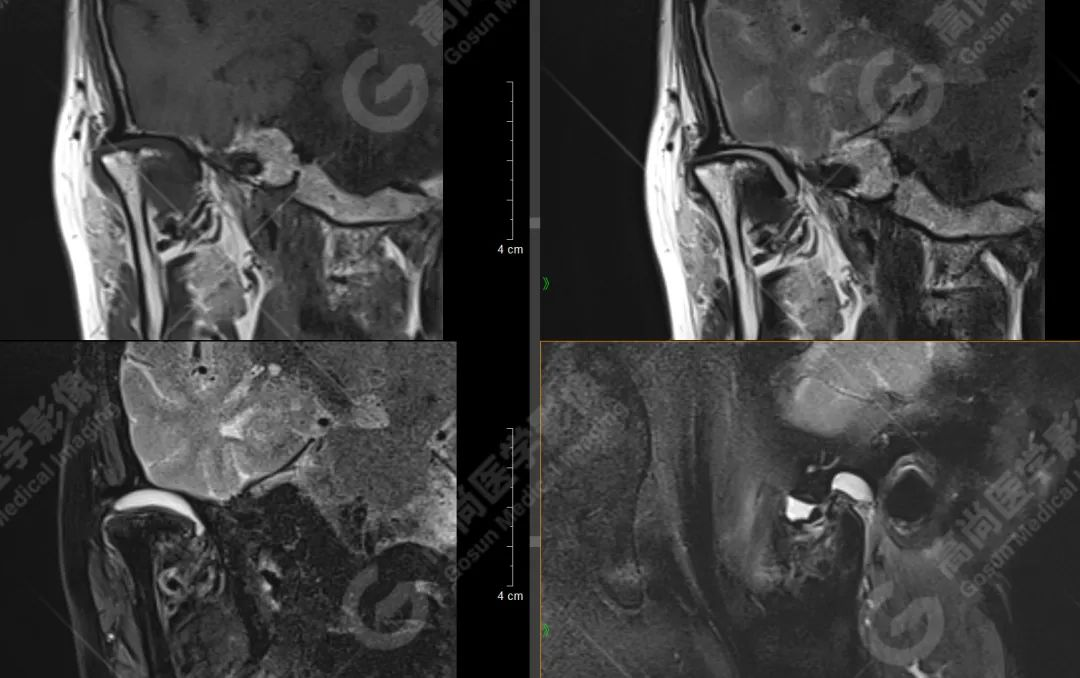

大多数颞下颌关节紊乱的诊断以病史和体格检查为主要依据。目前影像检查中颞下颌关节的核磁共振检查被视为观察关节囊内紊乱的金标准。CBCT和超声也有辅助诊断的价值。动态的下颌关节运动描记系统也为诊断提供了动态信息。